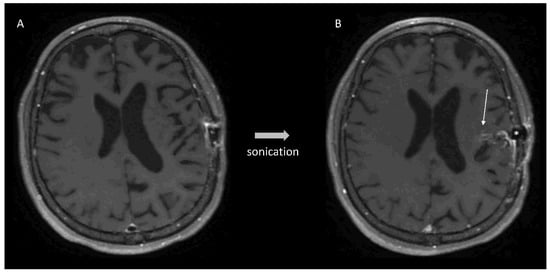

- Idbaih, A.; Canney, M.; Belin, L.; Desseaux, C.; Vignot, A.; Bouchoux, G.; Asquier, N.; Law-Ye, B.; Leclercq, D.; Bissery, A.; et al. Safety and Feasibility of Repeated and Transient Blood-Brain Barrier Disruption by Pulsed Ultrasound in Patients with Recurrent Glioblastoma. Clin. Cancer Res. 2019, 25, 3793–3801. [Google Scholar] [CrossRef] [Green Version]

- Carpentier, A.; Canney, M.; Vignot, A.; Reina, V.; Beccaria, K.; Horodyckid, C.; Karachi, C.; Leclercq, D.; Lafon, C.; Chapelon, J.-Y.; et al. Clinical Trial of Blood-Brain Barrier Disruption by Pulsed Ultrasound. Sci. Transl. Med. 2016, 8, 343re2. [Google Scholar] [CrossRef] [PubMed]

- Horodyckid, C.; Canney, M.; Vignot, A.; Boisgard, R.; Drier, A.; Huberfeld, G.; François, C.; Prigent, A.; Santin, M.D.; Adam, C.; et al. Safe Long-Term Repeated Disruption of the Blood-Brain Barrier Using an Implantable Ultrasound Device: A Multiparametric Study in a Primate Model. J. Neurosurg. 2017, 126, 1351–1361. [Google Scholar] [CrossRef] [PubMed] [Green Version]